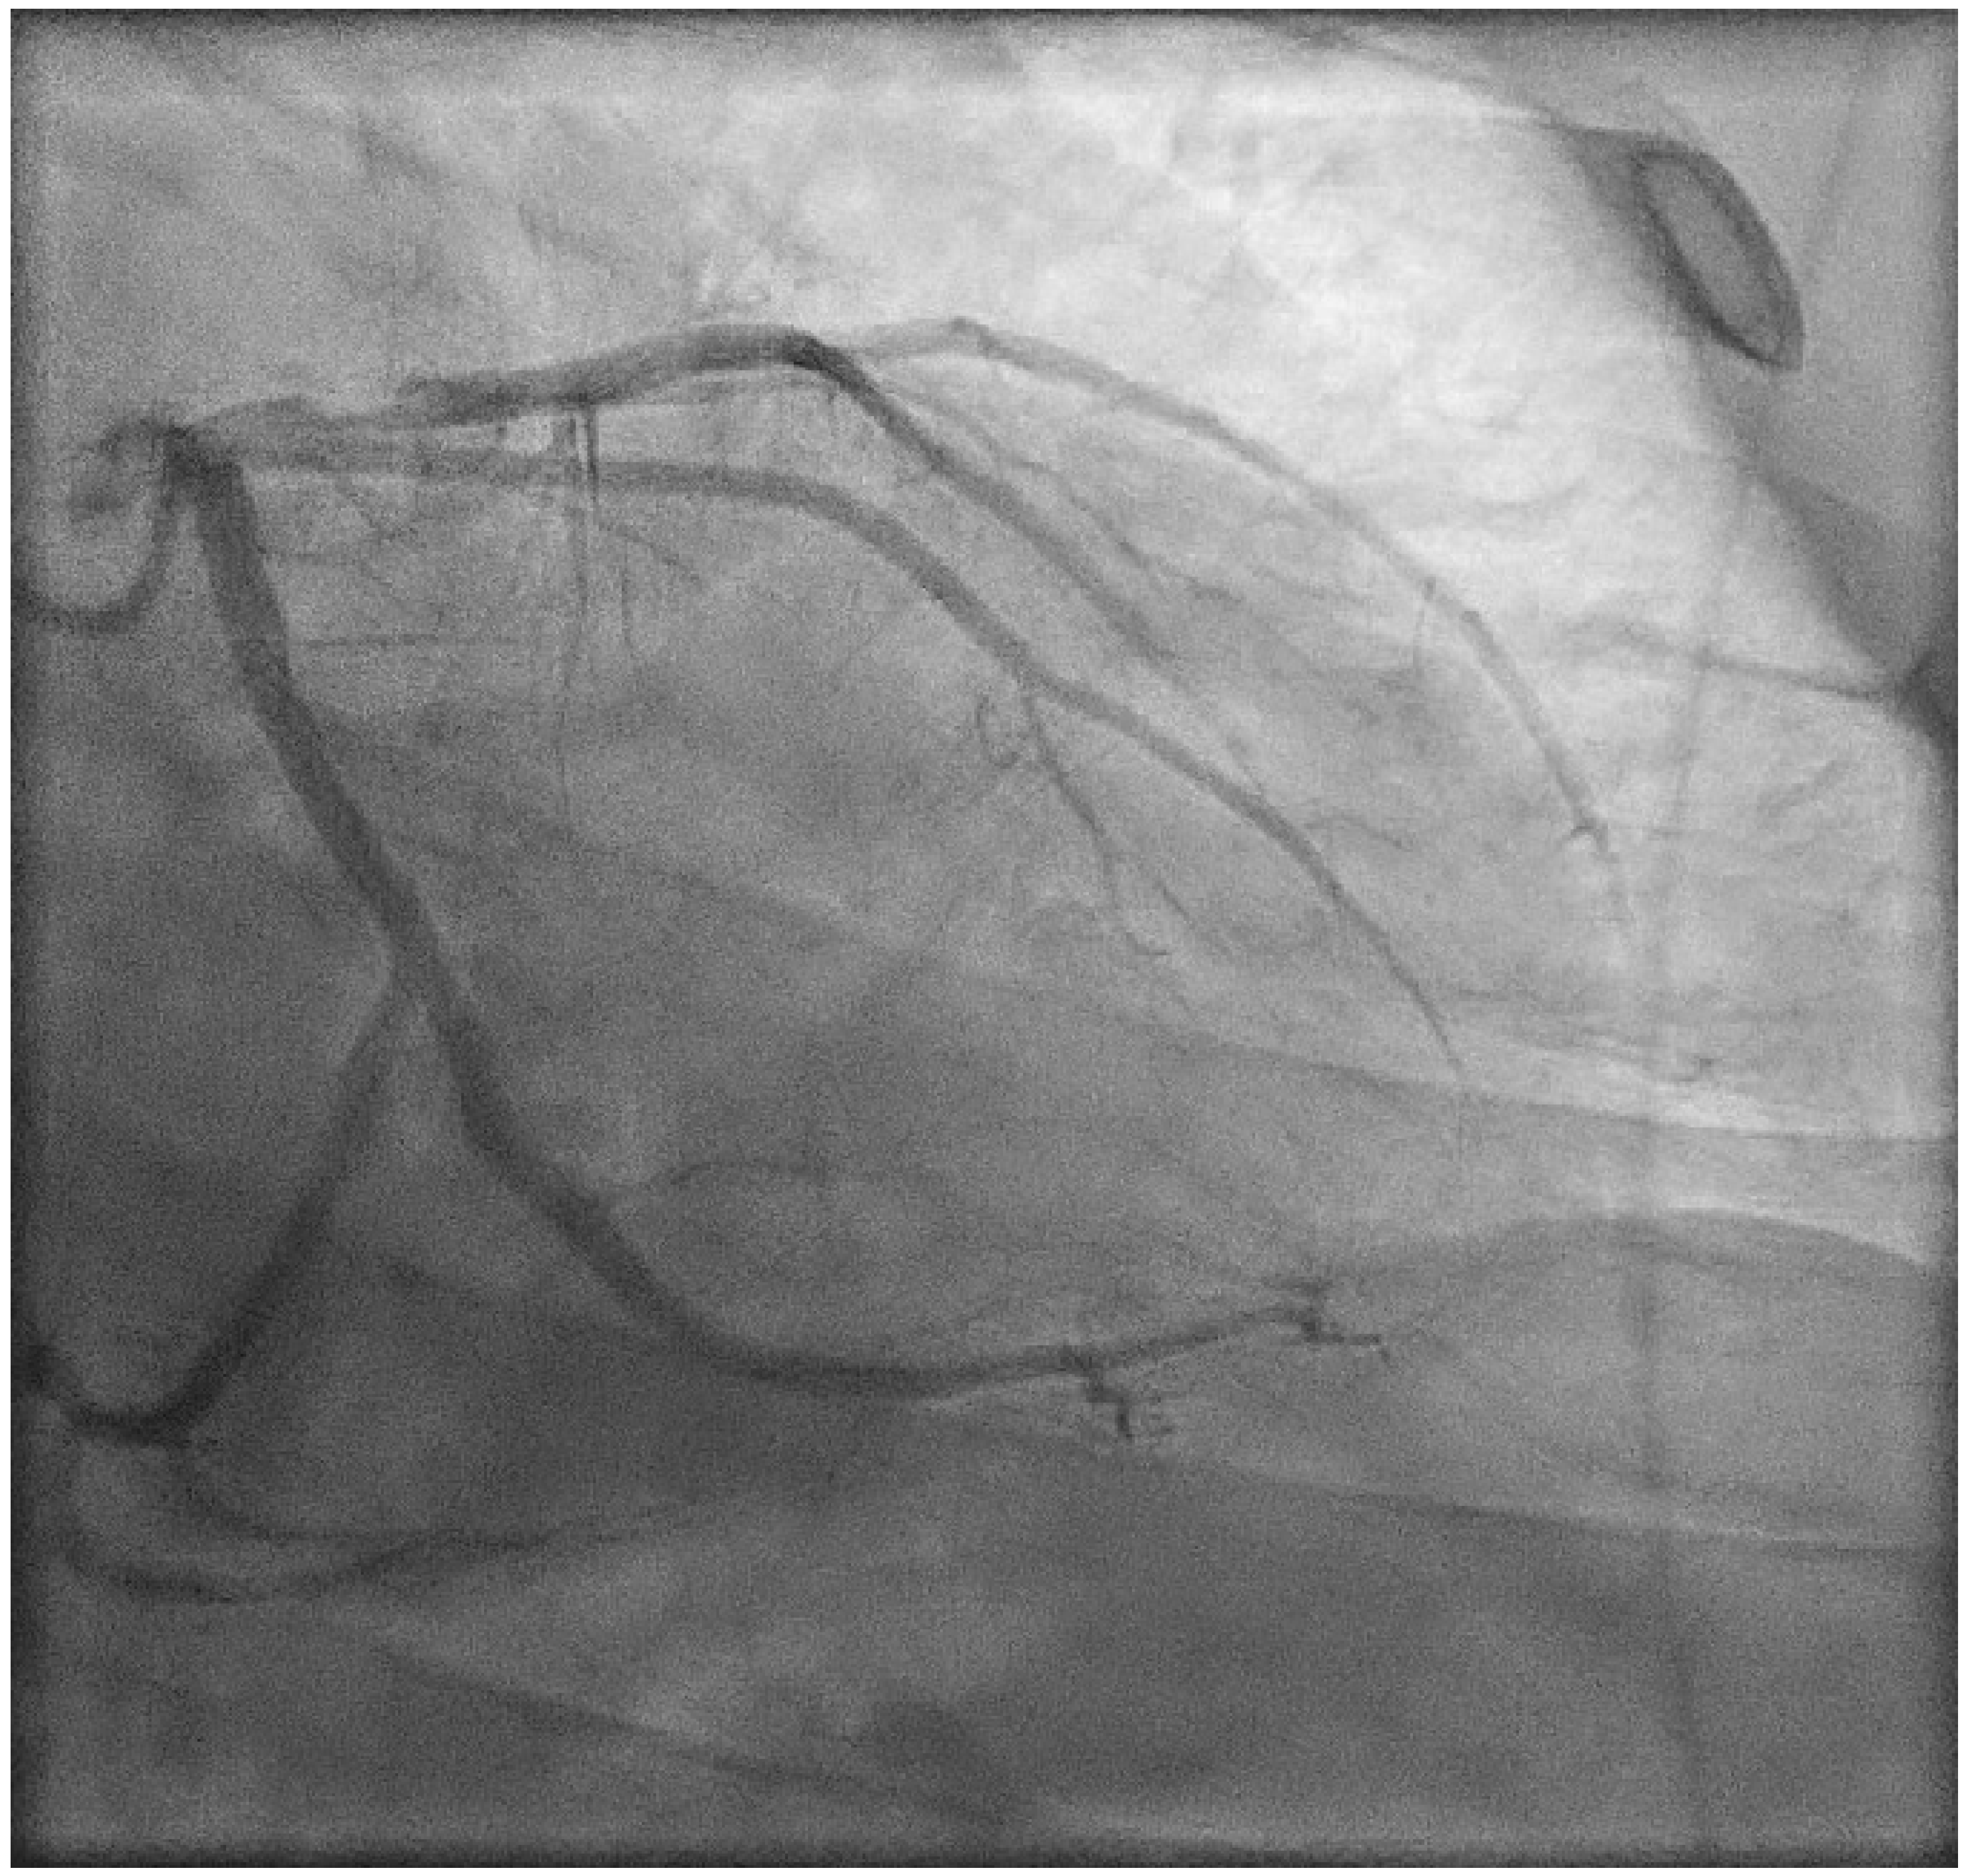

2. Case Presentation